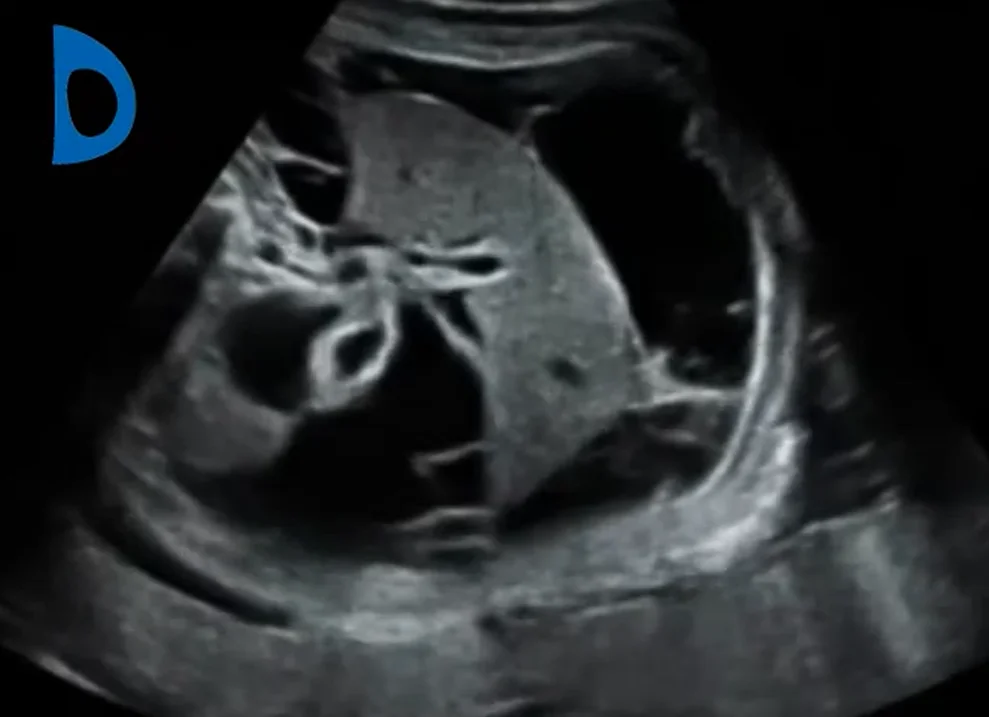

Viêm phúc mạc phân su bào thai (Meconium Peritonitis)

• Viêm phúc mạc phân su bào thai (Meconium Peritonitis)